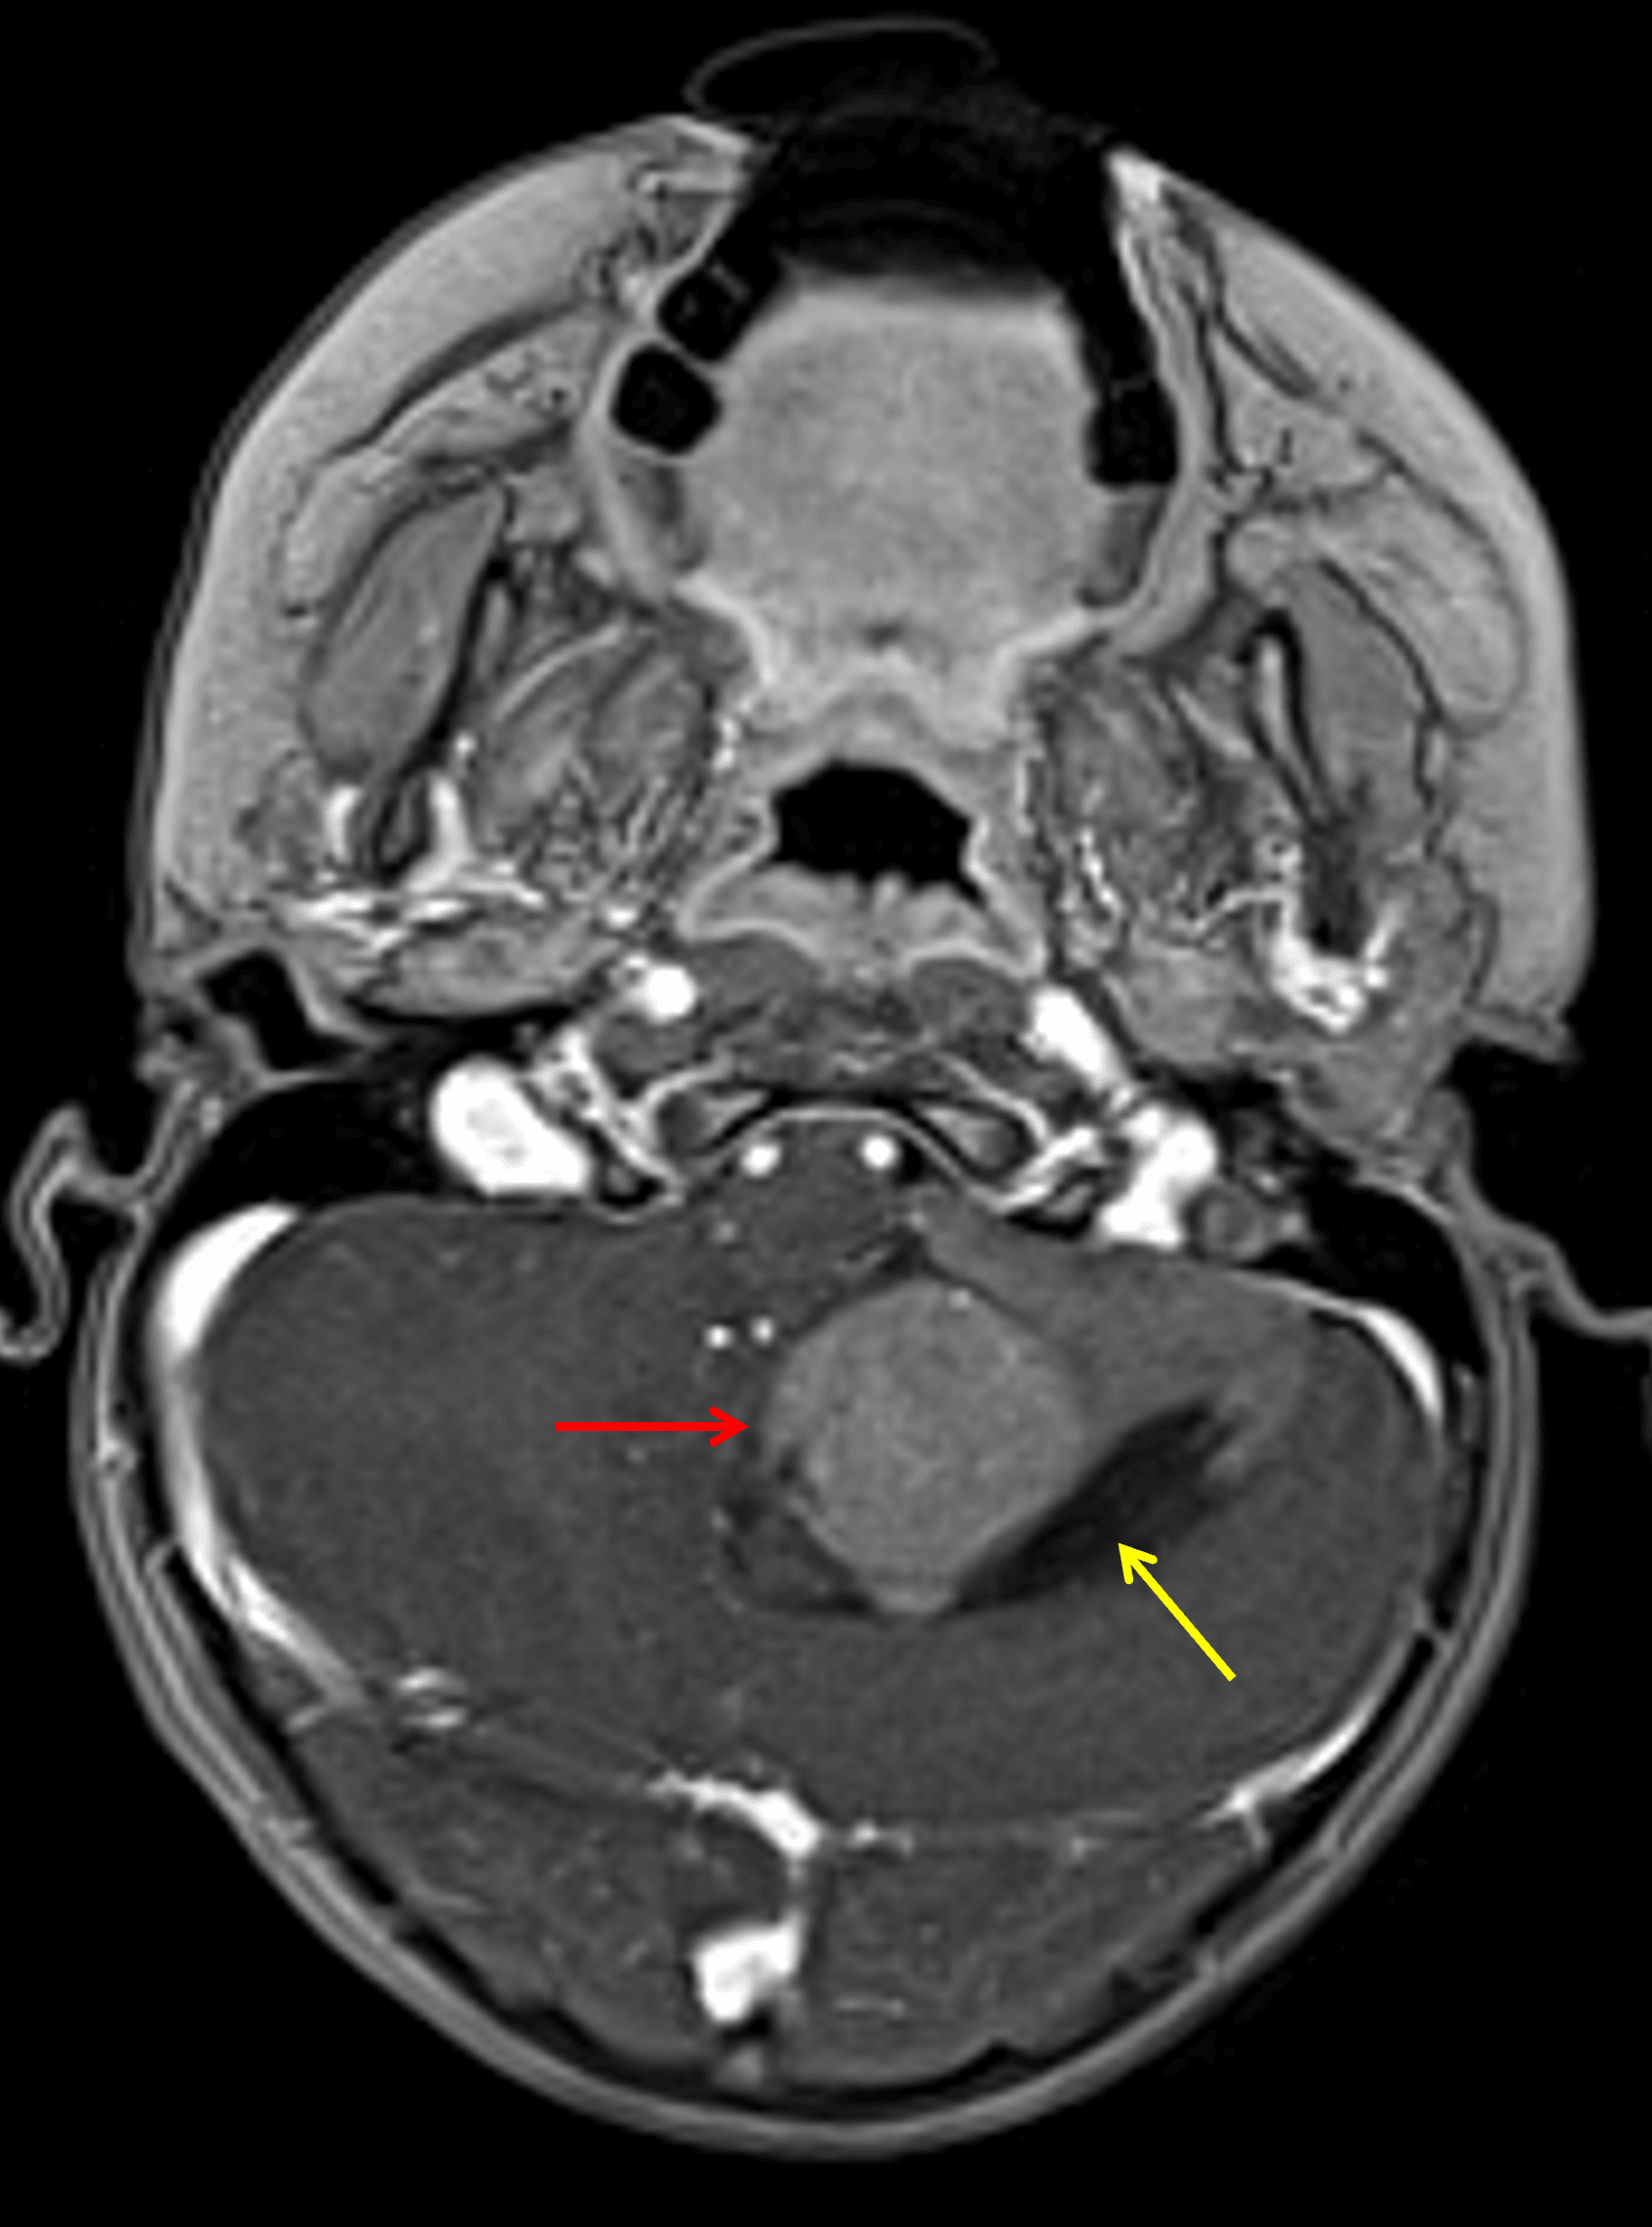

Enhancing mass centered in the left cerebellar hemisphere (red arrow) with a peripheral cystic component (yellow arrow).

• T1 hypointense, slightly T2 hyperintense mass centered in the inferior aspect of the left cerebellar hemisphere with diffuse enhancement and mild diffuse restricted diffusion

• Crescentic cystic components along the periphery of the mass

• Mild adjacent parenchymal edema

• Corresponding mass effect with obstructive hydrocephalus at the level of the fourth ventricle and mild upward transtentorial herniation